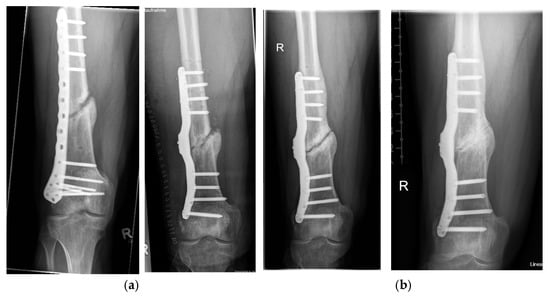

Long-Term Evaluation of Bone Healing Monitoring Using an Instrumented Plate with Measurement Sensors (Smart Implant) over 10 Years

by Arndt P. Schulz, Birgitt Kowald, Matthias Münch, Klaus Seide, Nils Weinrich, Tobias Barth and Benjamin Kienast

Sensors 2025, 25(18), 5779; https://doi.org/10.3390/s25185779 - 16 Sep 2025

A total of 66 smart implants were included. As a measure of bony stability, the relative elastic compliance of the osteosynthesis was determined from the gradient between the applied external load and the measured implant load over the entire healing process. The healing [...] Read more.

A total of 66 smart implants were included. As a measure of bony stability, the relative elastic compliance of the osteosynthesis was determined from the gradient between the applied external load and the measured implant load over the entire healing process. The healing process of non-unions of the femur with a smart implant was tracked by telemetric measurements over a timespan of up to 10 years. The measurements of the longest healing process show a very slow but constant decrease in force transmission over the implant, radiological findings over 10 years show corresponding consolidation until bony healing. The use of a telemetrically instrumented bone plate, a so-called smart implant, to monitor the healing process is a successful procedure to support the clinician in his decision to take further surgical measures or to wait until healing occurs. Full article